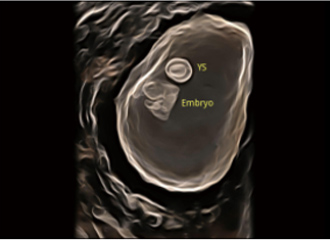

临床图像